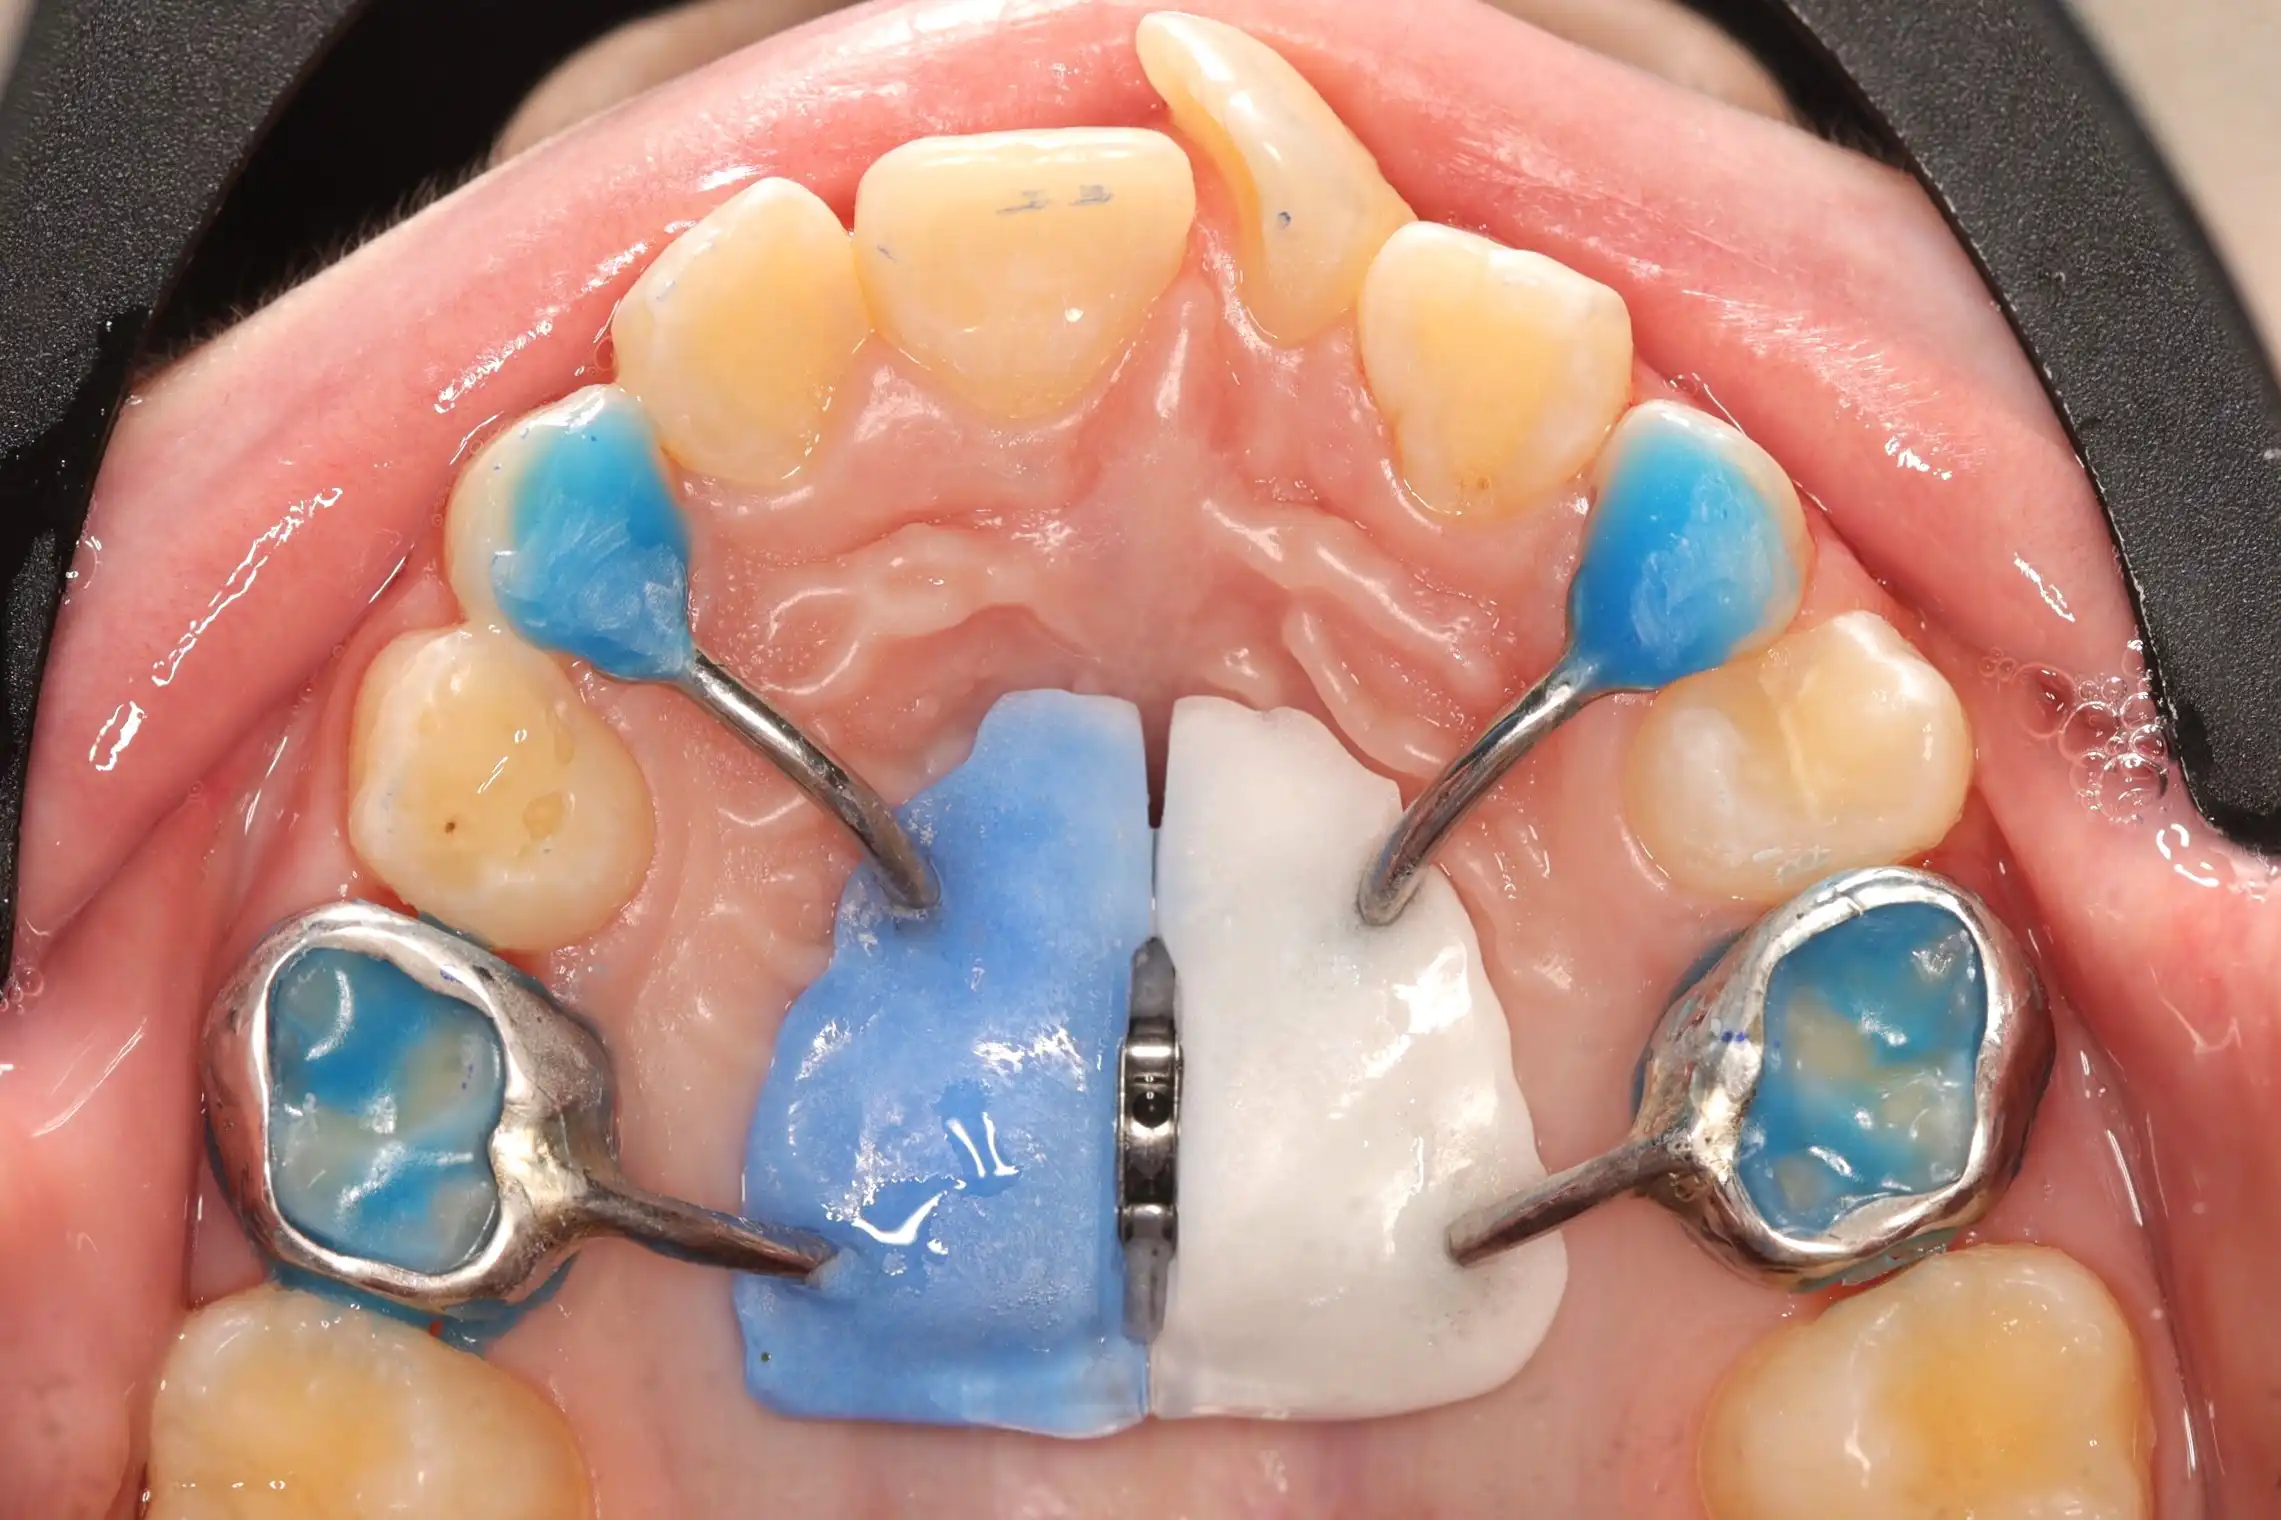

до

Лікування розпочато з розширення верхньої щелепи за допомогою незнімного апарату Marco Rosa, що дозволило сформувати необхідний простір. Далі проведена корекція положення різців із використанням часткової металевої брекет-системи 2х4, яка забезпечує точний контроль навіть на ранніх етапах формування прикусу.